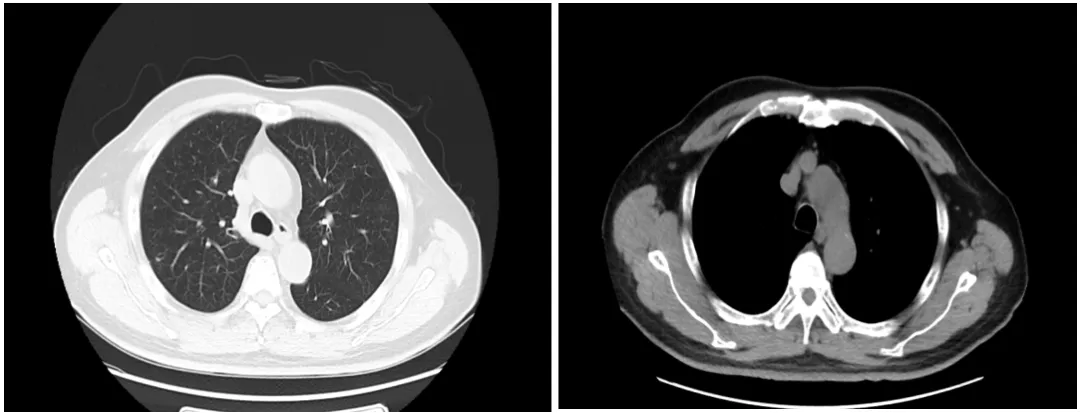

CT影像学检查(2025-08-13)

• 胸部CT:

肺(平扫):与2025-02-06前片对比,双肺多发实性结节较前明显减小,部分消失,提示转移瘤。

• 腹部及盆腔CT:

与2025-02-06双肾+输尿管CT平扫对比:前列腺较前明显减小及双侧精囊腺改变,腹主动脉及双侧髂动脉旁多发肿大淋巴结较前明显减小。